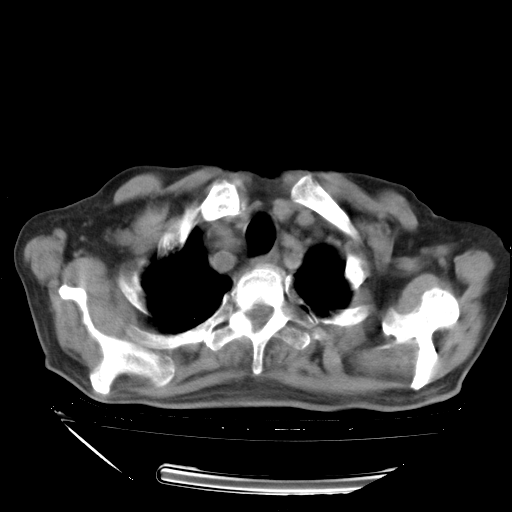

甲强龙80mg/日+抗结核治疗(异烟肼+利福霉素+乙胺丁醇)10天。复查肺部CT。

治疗10天肺部CT